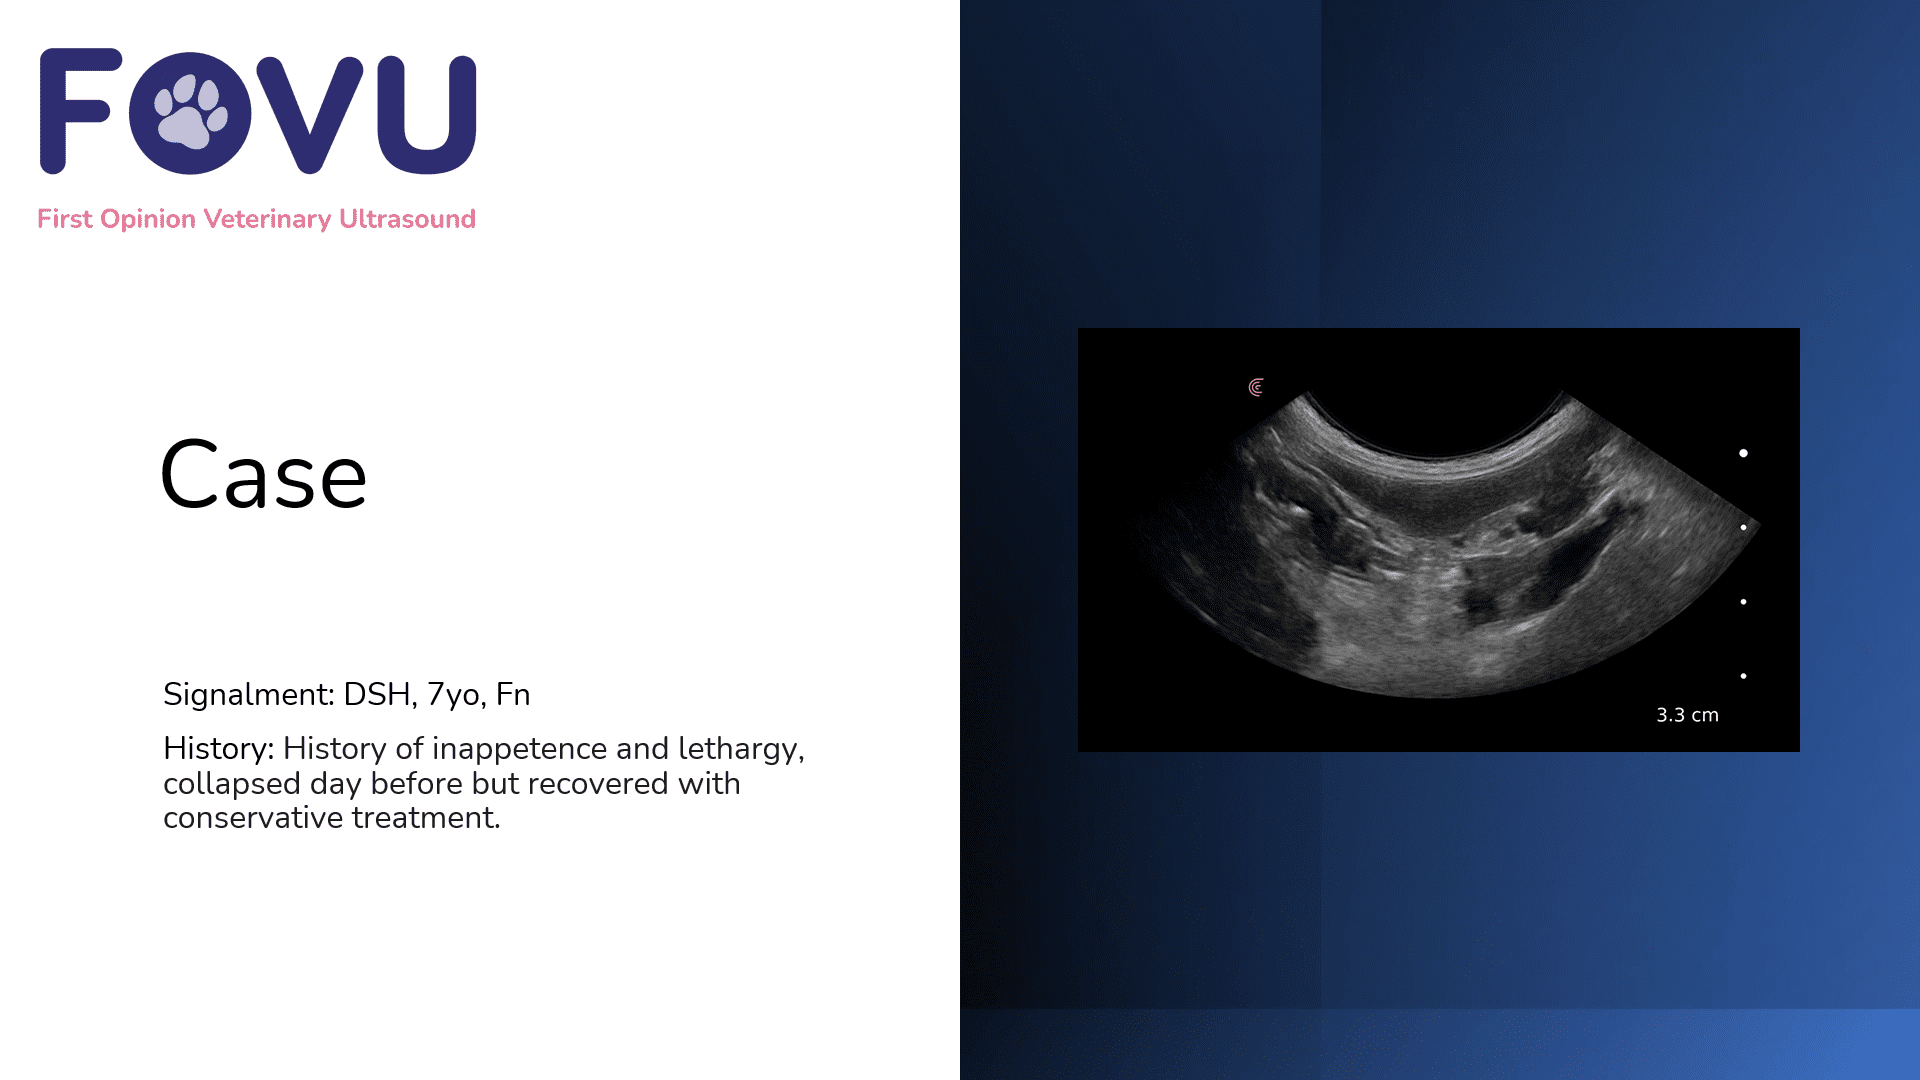

Feline Renal Infarcts

View Post